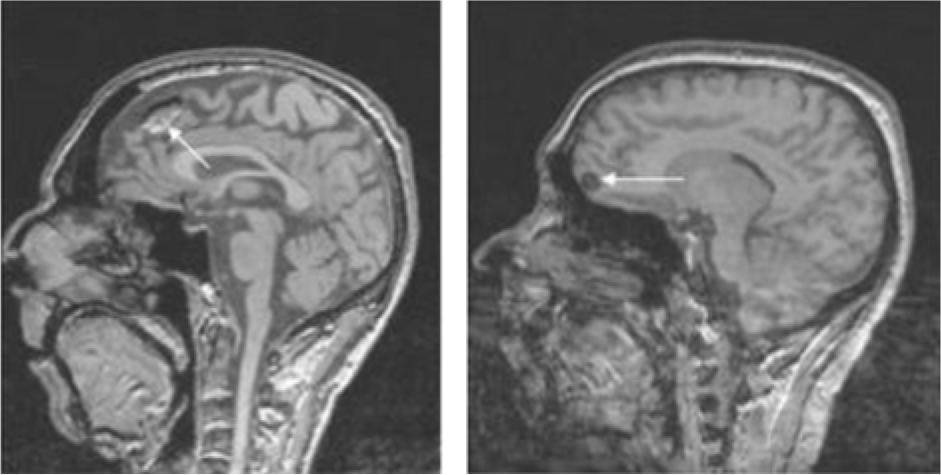

To simply give the reader a visual representation of the problem, we present the images in Figures 1–3 where accidentalomas were highlighted during some research projects conducted by our group. The research projects concerned healthy subjects and patients with schizophrenia who were investigated for relationships between cerebral activation and cognitive or emotional functioning.

Figure 1: Sagittal T1 sections: Heterogeneous frontal mass (in hyper- and hyposignals) in the image on the left and a homogeneous hyposignal nodular lesion on the right. These images could correspond to tumor lesions – further investigation is needed.